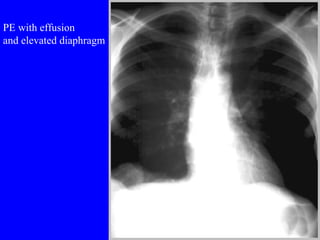

PE with effusion and elevated diaphragm

PE with effusionand elevated diaphragm